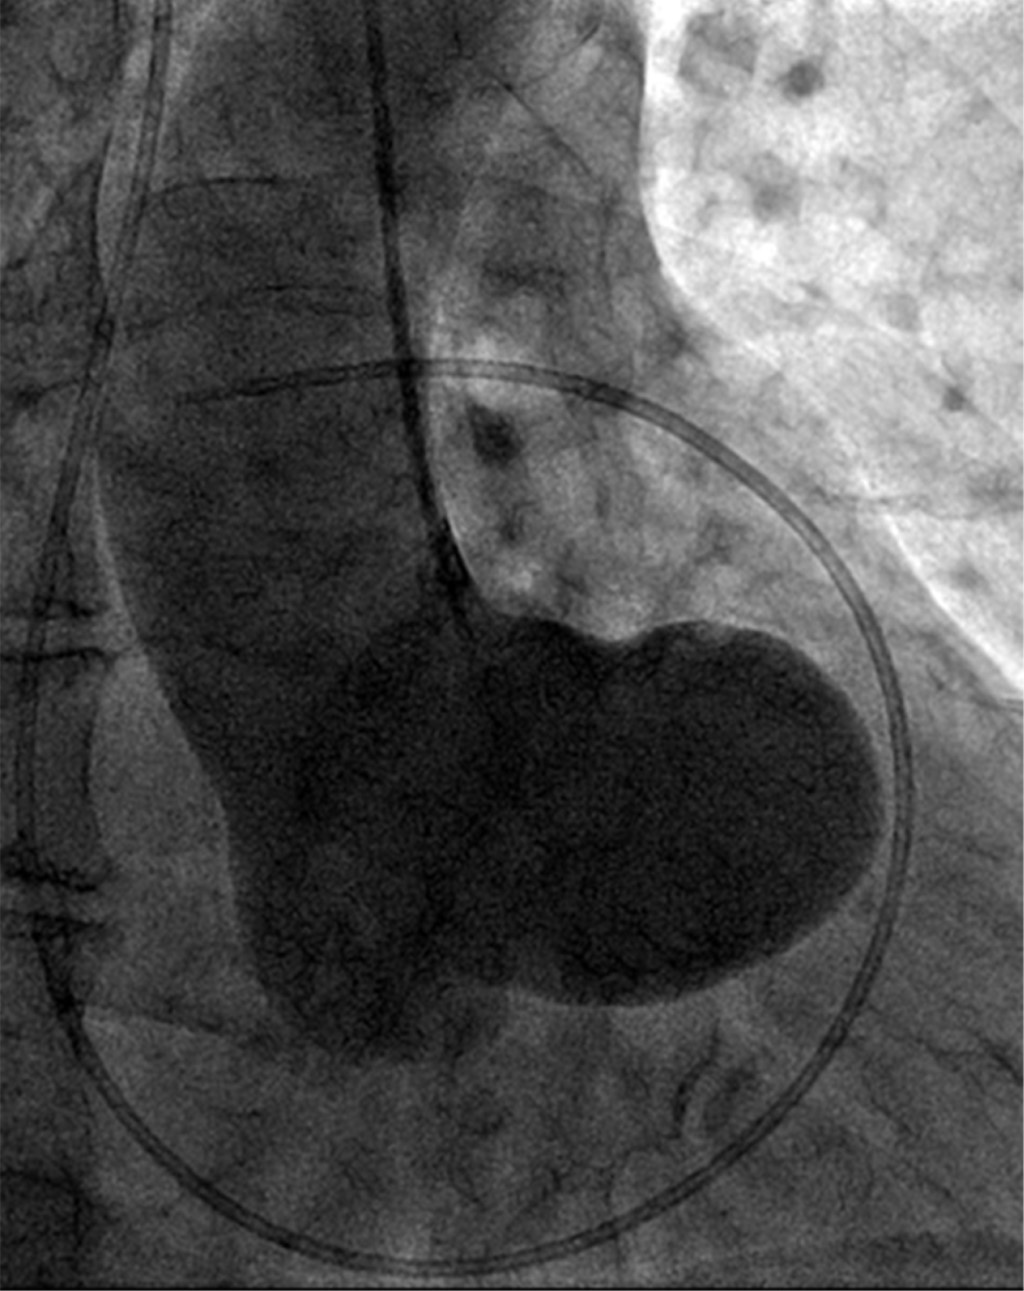

Los aneurismas del seno de Valsalva son dilataciones congénitas o adquiridas de la pared del seno aórtico a nivel justo por encima de las tres cúspides de la válvula aórtica, que pueden ser casos asintomáticos o fatales si se rompen, más frecuentemente hacia las cavidades cardiacas derechas. Estos casos son relativamente raros. Presentamos el caso de un varón de 72 años remitido por sospecha de soplo pulmonar. La evaluación reveló un aneurisma del seno de Valsalva derecho, que causaba compresión del tracto de salida del ventrículo derecho (TSVD). El ecocardiograma, la tomografía computarizada y el aortograma revelaron imágenes interesantes y evocadoras. El paciente recibió una reparación quirúrgica mid-cap. Este artículo revisa y discute la literatura actual y presenta el caso.

Figura 4